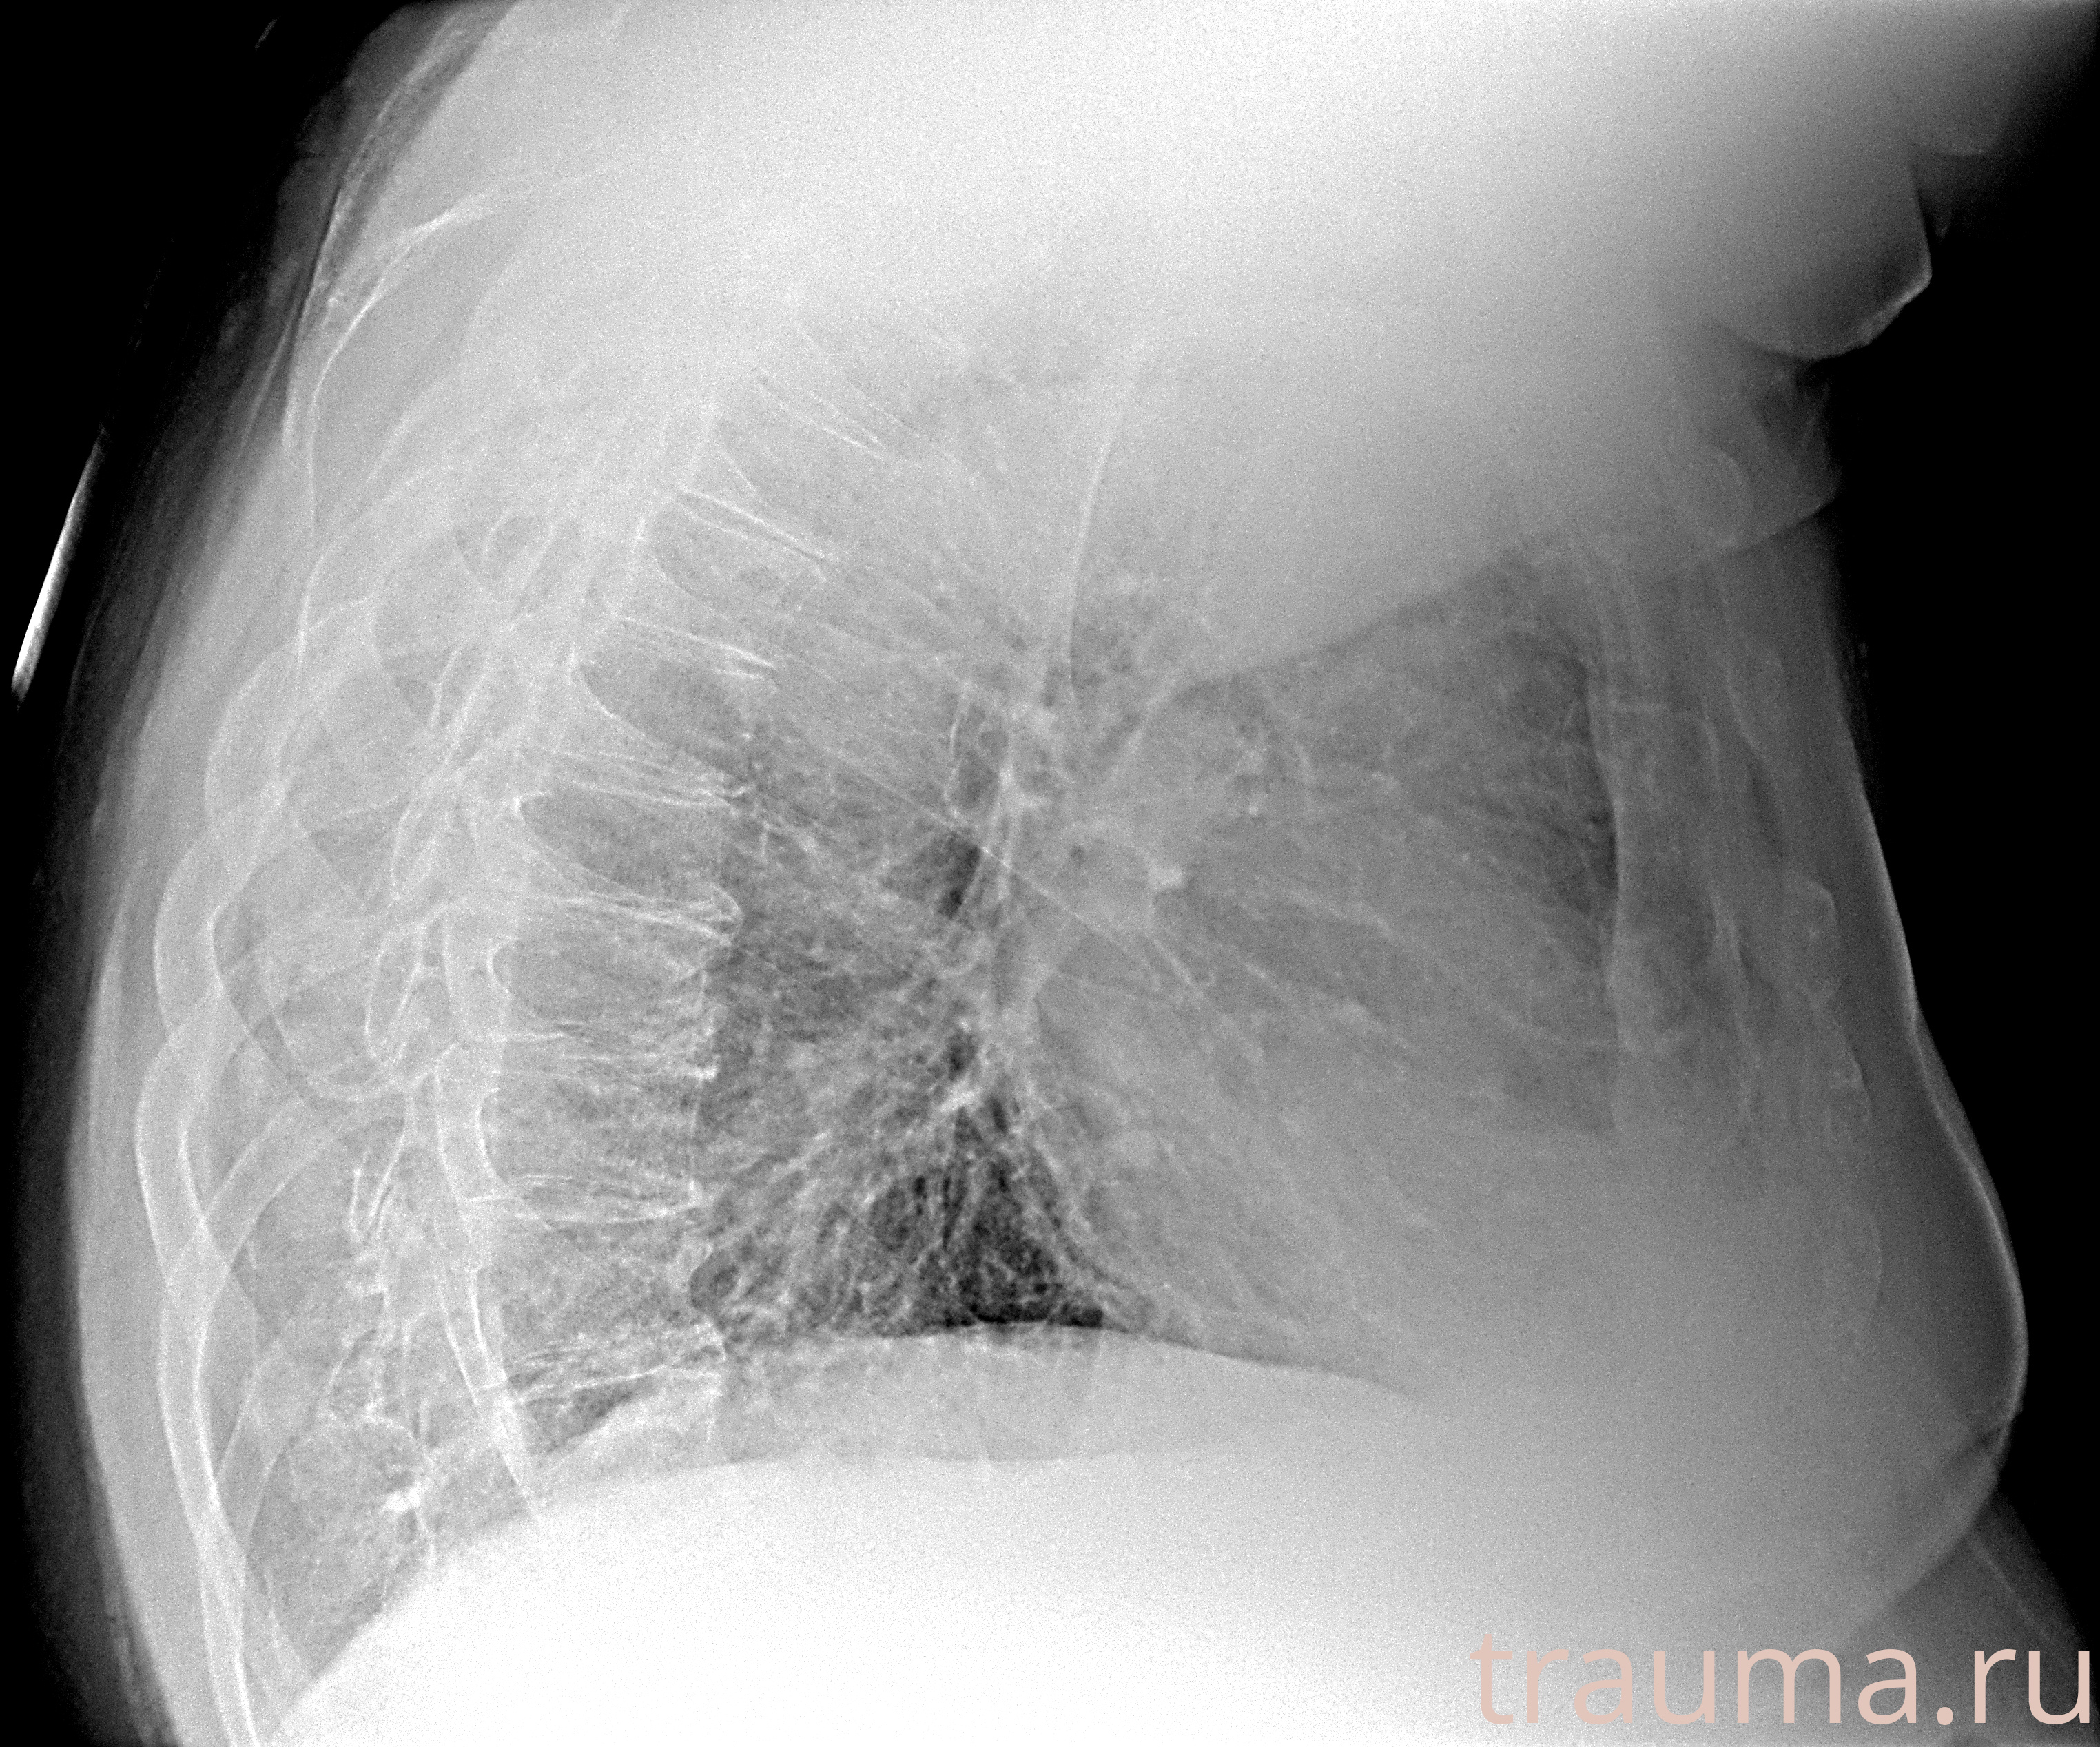

Рентгенограммы

Рентген на дому: по вашему адресу приезжает врач-рентгенолог, травматолог-ортопед с мобильным рентгеновским аппаратом, проводит диагностику травмы или заболевания, делает необходимые рентгенограммы, дает рекомендации по дальнейшему лечению. Получить качественные снимки в домашних условиях возможно благодаря уникальной методике, разработанной МосРентген Центром для института  Склифосовского

Яркость: 1   Контраст: 1   Инвертировать: 0 Увеличение: 1

Перетаскивайте мышь вверх/вниз для контраста, влево/право для яркости. Прокрутка колесом изменяет масштаб. Нажмите Сбросить для возврата к исходному изображению. При увеличении держите мышь в той области, которую хотите рассмотреть.